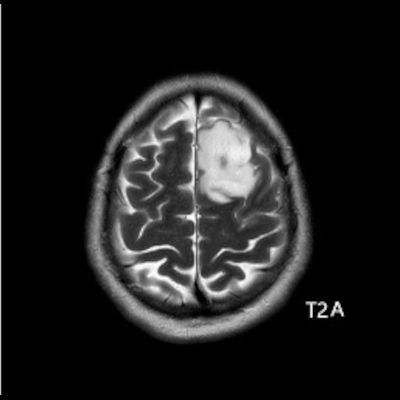

- Sol frontal kortikal-subkortikal yerleşimli aksiyel T2A görüntüde hiperintens sinyal özelliği gösteren (oklar) ve FLAIR görüntüde sinyali ağırlıklı olarak baskılanan (oklar) kitlesel lezyon izleniyor. Lezyon T1A görüntüde hipointens olup post-kontrast T1A görüntüde bu düzeyde patolojik kontrastlanma izlenmiyor (oklar).

- FLAIR’de T2’ye benzer şekilde hiperintens görünür. Ancak T2–FLAIR mismatch bulgusu, bu tümör tipi için oldukça karakteristiktir.

- T2–FLAIR mismatch bulgusu, T2AG’de homojen hiperintensite ile FLAIR görüntüde santral sinyal baskılanmasının ve çevrede hiperintens halka görünümünün bulunduğu bir fenomendir. Bu bulgu, özellikle IDH-mutant, 1p/19q kodelesyonu olmayan astrositomları tanımlamada oldukça özgül bir biomarker olarak literatürde vurgulanmıştır. Ayırıcı tanıda akla gelmesi gereken oligodendrogliomlarda T2/FLAIR mismatch bulgusu genellikle görülmez.

- Olgumuzda T2-FLAIR mismatch bulgusu mevcut olup, opere edilmiş ve tanısı histopatolojik olarak konulmuştur.